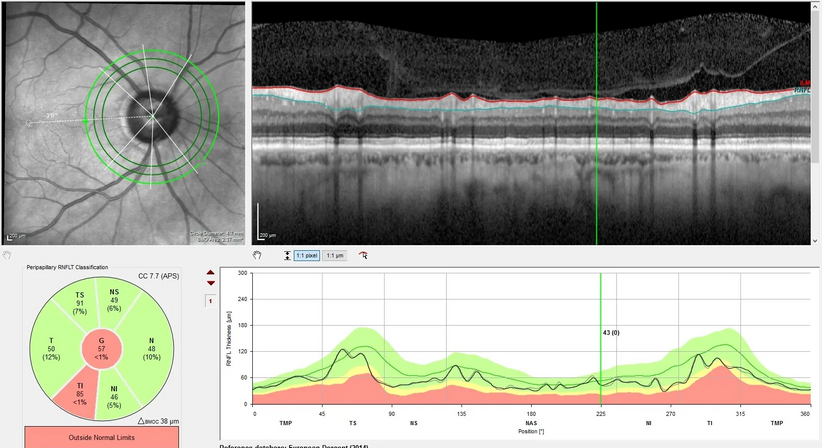

Zur umfassenden Abklärung eines Glaukoms werden in unserer Ordination eine Augendruckmessung (Tonometrie), eine klinische Untersuchung des Sehnervs mittels Mikroskop, eine hochauflösende Laser-Schichtbildaufnahme (OCT, optische Kohärenz Tomographie) des Sehnervs und der Nervenfaserschicht sowie eine Gesichtsfelduntersuchung (Perimetrie) standardmäßig durchgeführt.